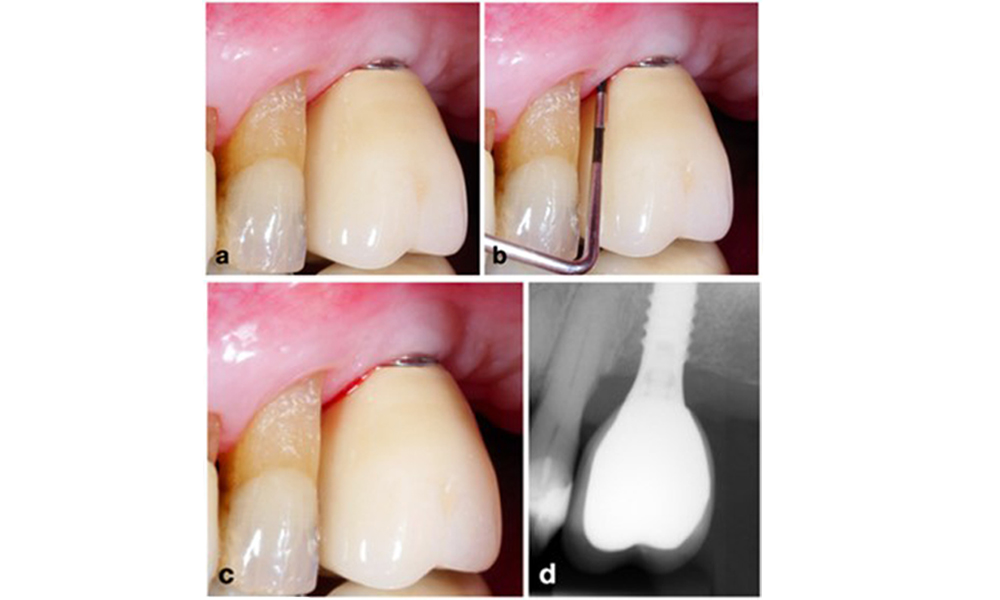

Management of peri-implantitis at implants judged as treatable consists of a non-surgical phase, which is often followed by surgical intervention. For the non-surgical approach, similar measures as those applied for the treatment of peri-implant mucositis are used; based on laboratory experiments air-polishing devices with a subgingival nozzle appear to provide certain advantages in terms of biofilm removal, compared to hand- or ultrasonic instruments (Herrera et al. 2023; Moharrami et al. 2019; Ronay et al. 2017) (figure 9).

Patient case with peri-implantitis. The non-surgical treatment is performed by using the supragingival (a-b) and subgingival handpiece of an air-polishing device (c-d). Removing the supra-construction provides better access to the implant surface (d).

Figure 9. Patient case with peri-implantitis. The non-surgical treatment is performed by using the supragingival (a-b) and subgingival handpiece of an air-polishing device (c-d). Removing the supra-construction provides better access to the implant surface (d).

Yet, the non-surgical approach often has limitations in accessing the implant surface, leading to insufficient decontamination. This is indeed reflected in the clinic, where disease resolution after non-surgical treatment of peri-implantitis is rather unpredictable and recurrence is observed for most cases, i.e., disease resolution was reported to occur only in less than every second case (Ramanauskaite et al. 2021). Therefore, the outcome of non-surgical treatment needs to be evaluated after about 6 weeks, and in cases of moderate or advanced peri-implantitis, surgery should be expected.